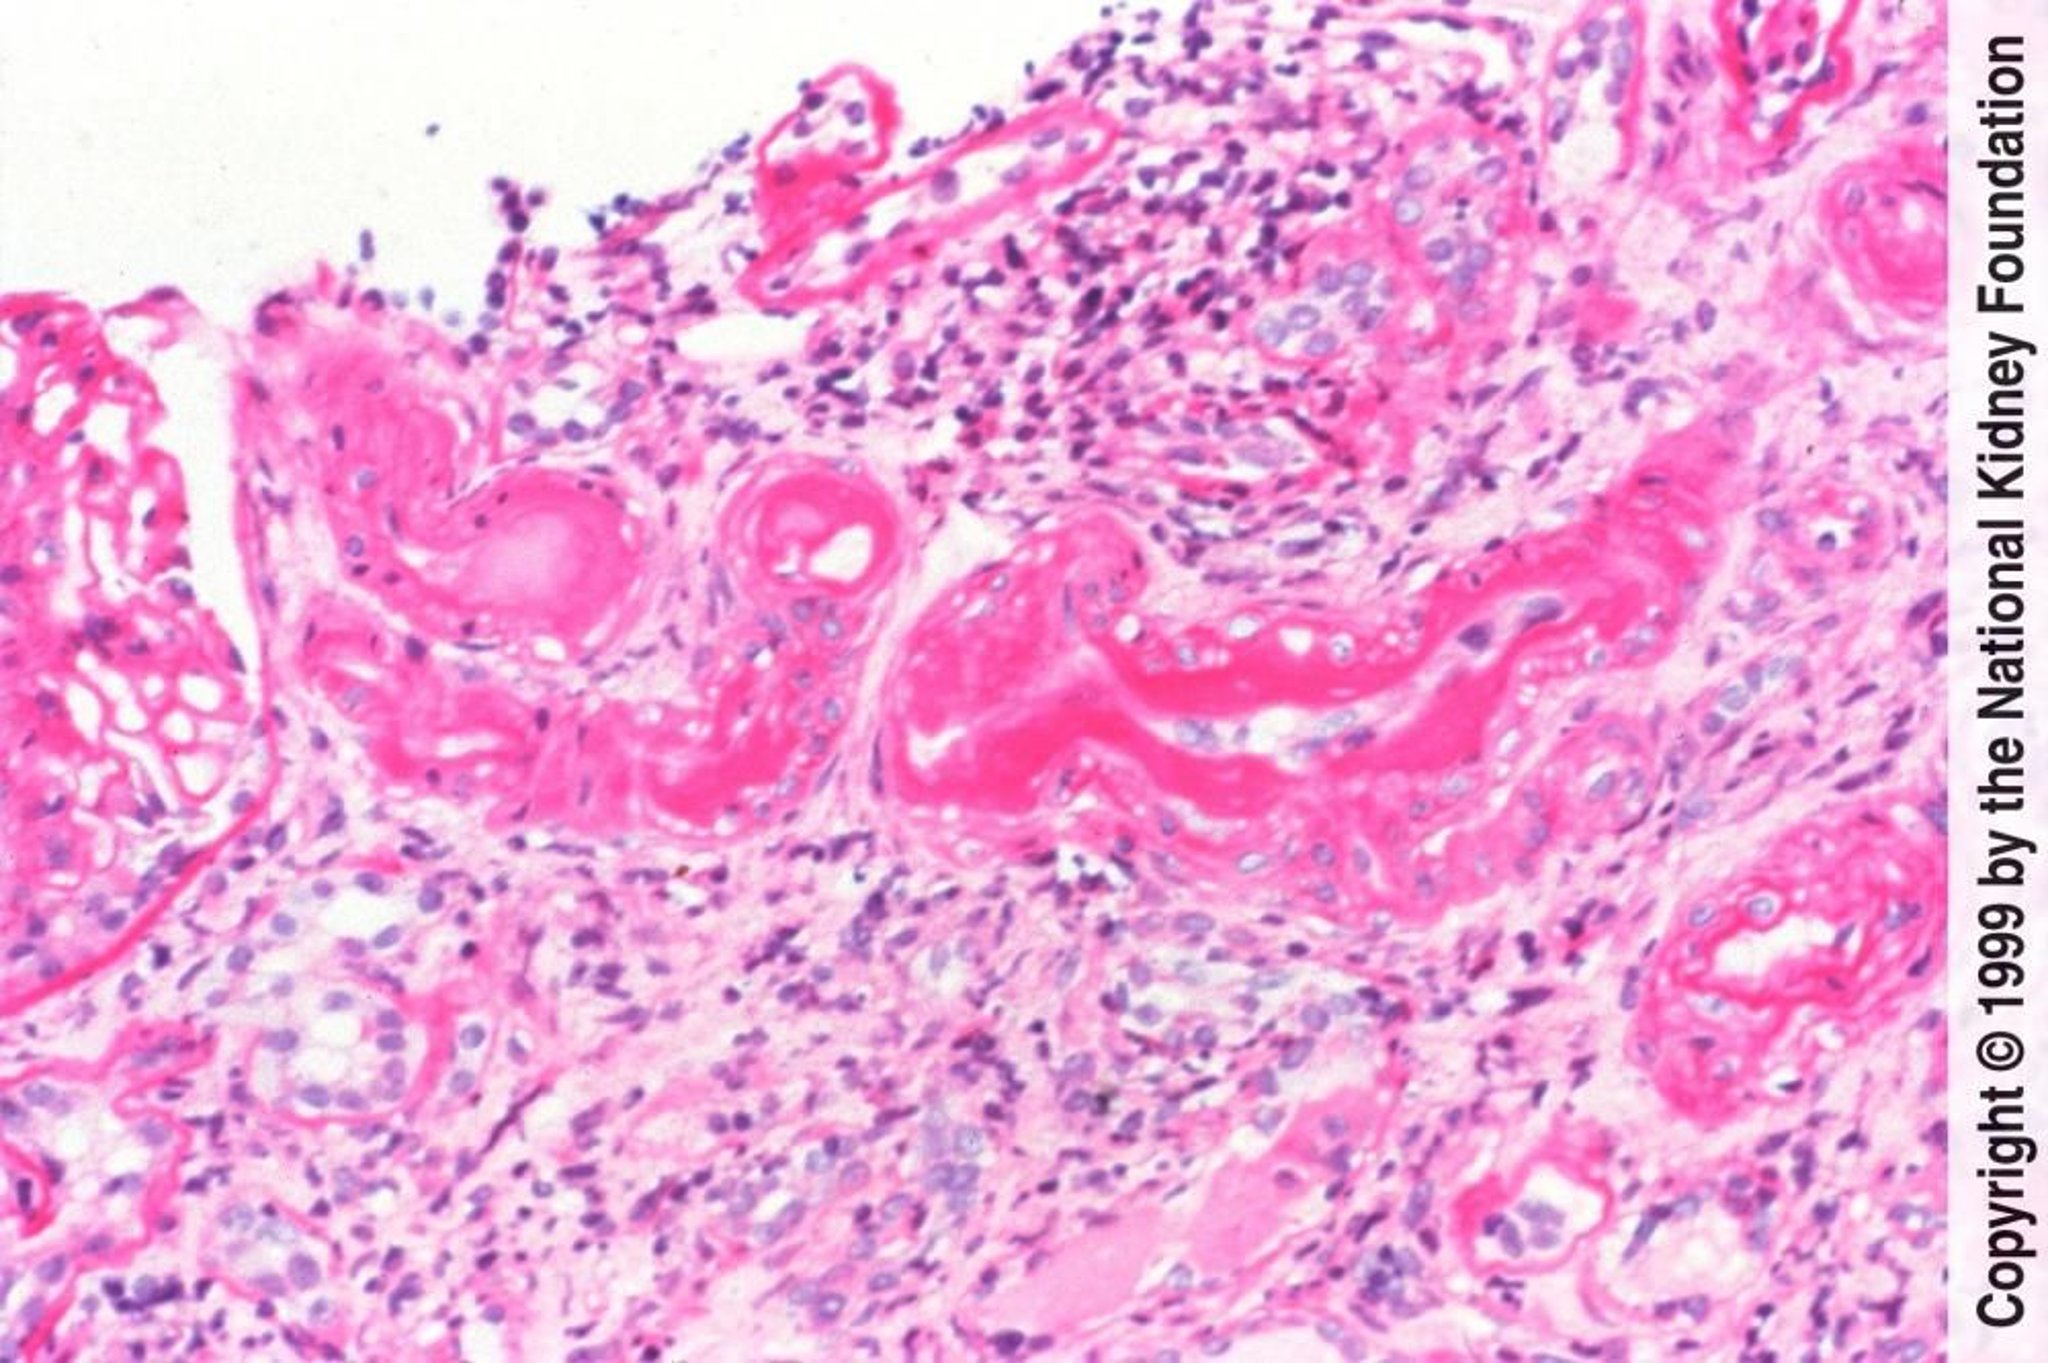

Néphrosclérose hypertensive artériolaire bénigne

La néphrosclérose artériolaire bénigne hypertensive est caractérisée histologiquement par une hyalinose artériolaire provoquée par l'insudation de protéines plasmatiques et un épaississement de la média causé par l'hypertrophie et l'hyperplasie des cellules musculaires lisses vasculaires (coloration à l'acide périodique Schiff, × 200).

Image fournie par Agnes Fogo, MD, and the American Journal of Kidney Diseases' Atlas of Renal Pathology (voir www.ajkd.org).